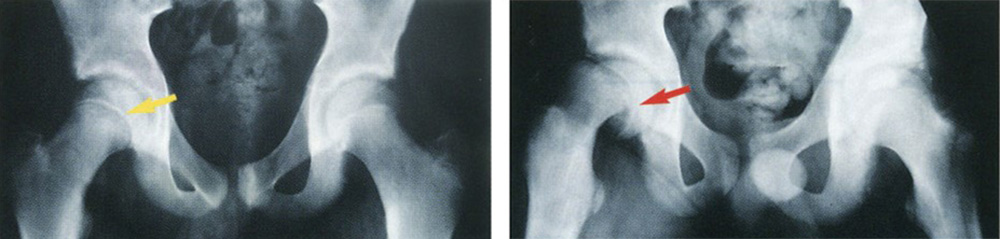

Typical hip joint (left) and slipped capital femoral epiphysis (right).

Slipped capital femoral epiphysis (SCFE; pronounced SKIFF-ee) is when the top of the thighbone slips out of place. SCFE is a kind of break (fracture).

To understand SCFE, it helps to know a little about what the hip joint looks like. The top part of the thighbone (femoral head) is shaped like a ball. It fits into the hip socket. The ball is connected to the straight part of the thighbone by the . The growth plate is an area of cartilage where bone is still growing. The part of the thighbone just below the growth plate is called the femoral neck.

In SCFE, the top or cap of the ball slips off the femoral neck through the growth plate. Think of the ball as being like a scoop of ice cream that slips off its “cone,” the thighbone.